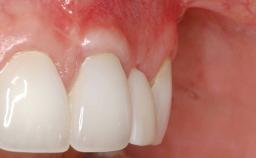

Early Implant Placement, Contour Augmentation, and Autologous Connective-Tissue Graft Using a Tunneling Technique to Replace an Upper Incisor with Generalized Gingival Recession

Variations in soft-tissue volume, evidenced either by an overabundance (Evian and coworkers 1993; Levine and McGuire1997; Dolt and Robbins 1997) or by a deficiency of soft or hard tissue can complicate implant-supported rehabilitations in the esthetic zone (Lorenzana 2008; Lorenzana and coworkers 2009). The present case illustrates the replacement of a failing upper left lateral incisor complicated by generalized severe gingival recession in the esthetic zone.